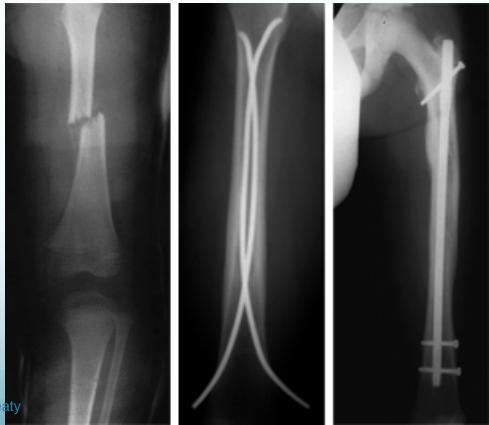

Femoral Shaft Fractures

Mechanism and Complications

- Mechanism: high energy

- Bleeding:

- Can easily loose 2L of blood

- Need good resuscitation

- Early fixation

Surgical Treatment

- IMN: Intramedullary nail / Locked(with screws)

- The treatment of choice

- Relative stability

- Allows early weight-bearing

Intramedullary Nailing

- IMN: Intramedullary nail

- Locked IMN (with screws)

Pediatrics Femur Fractures

Problems

- Bleeding - May bleed more than 1 L

Treatment Approaches

Conservative (up to 5-year-old)

- High remodeling rate

- Hip spica cast

- 1-2 cm shortening will be compensated by growth

- Monitor for mal-union

Operative (older children, >5 years)

- Accepted alignment, length & rotation

- Nailing better than plating

- Another surgery needed to remove implants